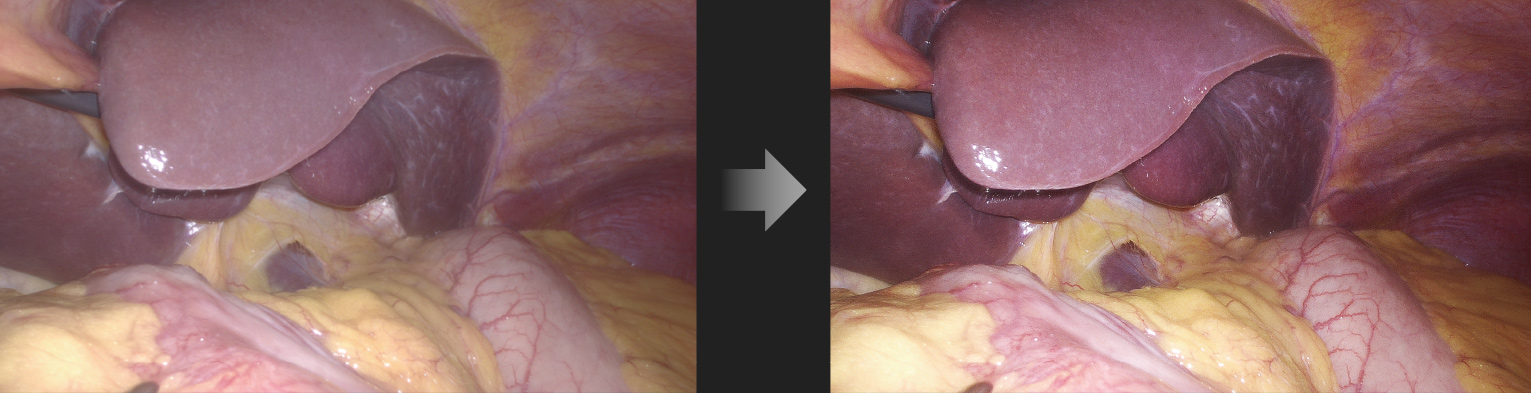

Automatic Scene Recognition, Intelligent Brightness Adjustment

Smart exposure: Determine different detection areas according to different scene and accurately match the exposure parameters without the need to manually switch department modes.

Laparoscope scene

Automatic dimming: The camera system can automatically adjust the intensity of the light source in real time according to the exposure requirements of the current image, and ensure appropriate brightness.